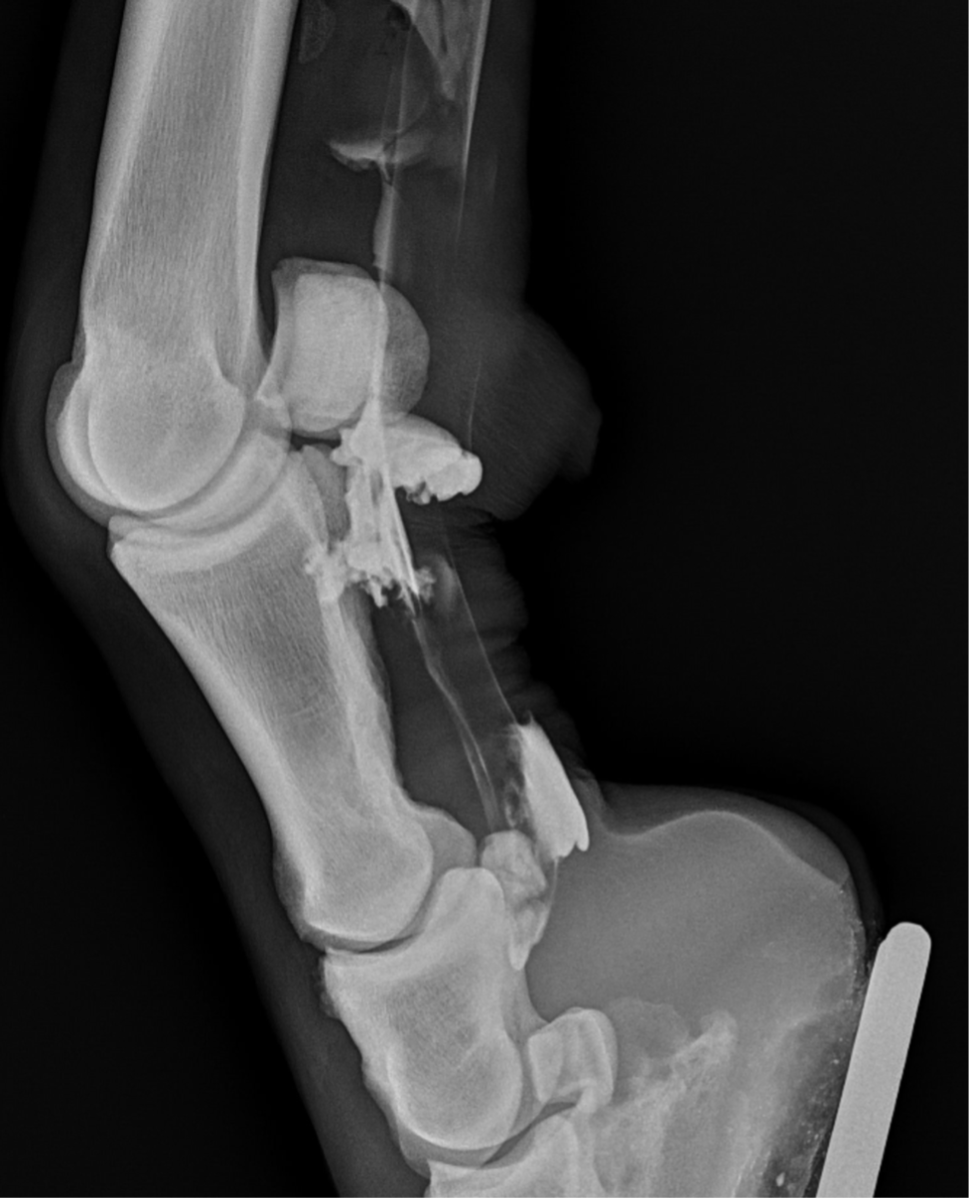

Recently, the gelding developed acute tenosynovitis of the left hind digital flexor tendon sheath (DFTS) following a competition. Despite the owner’s efforts, which included icing, wrapping, and confinement for seven days, there was no improvement in the effusion of the DFTS.

Upon further examination, contrast radiographs and ultrasound scans failed to identify any significant abnormalities apart from swollen synovium within the DFTS. To address this issue, our veterinary team administered 5mg of triamcinolone acetonide along with 20mg of HA, complemented by a compression wrap. Subsequently, the horse underwent a two-week confinement period in a small yard, followed by gradual reintroduction to exercise through 10 minutes of hand walking twice daily, with the distal limb wrapped for additional support.